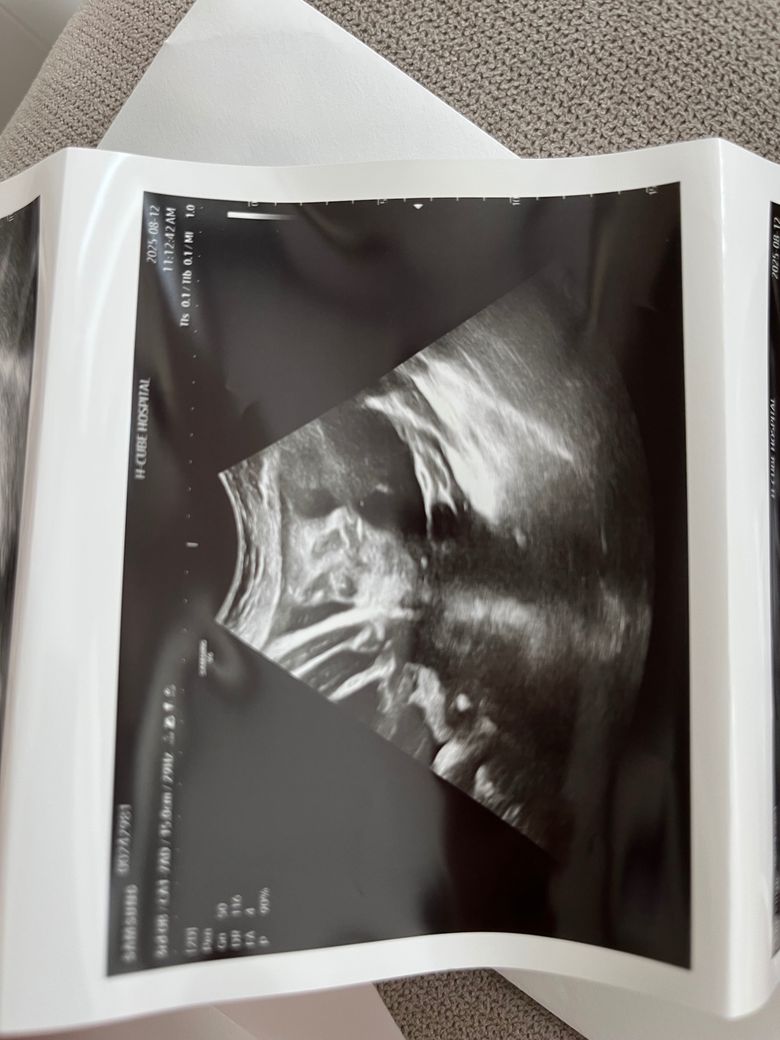

안녕하세요, 사진 순으로 24주차 입체초음파, 그 다음 두 장은 36주차 일반 초음파 사진입니다.

다름이 아니라 36주차 사진상 아이 눈 간격이 너무나 좁아보여서 걱정이 되어서 여쭈어봅니다..

옆으로 눌린 자세라 일시적으로 그렇게 보일 수 있는건지, 아니면 실제 저렇게 눈 간격이 좁은 아이의 경우도 있는지 궁금합니다.

초음파는 3차원의 물체를 2차원적 영상으로 표현하지요. 공간상 왜곡으로 보이며, 사실 특별한 소견으로 생각되지 않아요.

다운증후군일 경우에도 눈이 좁아보이거나 할 수 있지만, 이는 초음파로 눈의 간격을 확인하는 것이 아닌 목덜미 투명대, 심장구조 등을 보면서 평가하는 것이지, 질문자분이 걱정하시는 바가 아닙니다. 그리고 관련해서 문제가 있었다면 진즉에 담당 주치의가 설명을 했을 부분입니다.

너무 큰 걱정 안하셔도 되리라 생각됩니다.